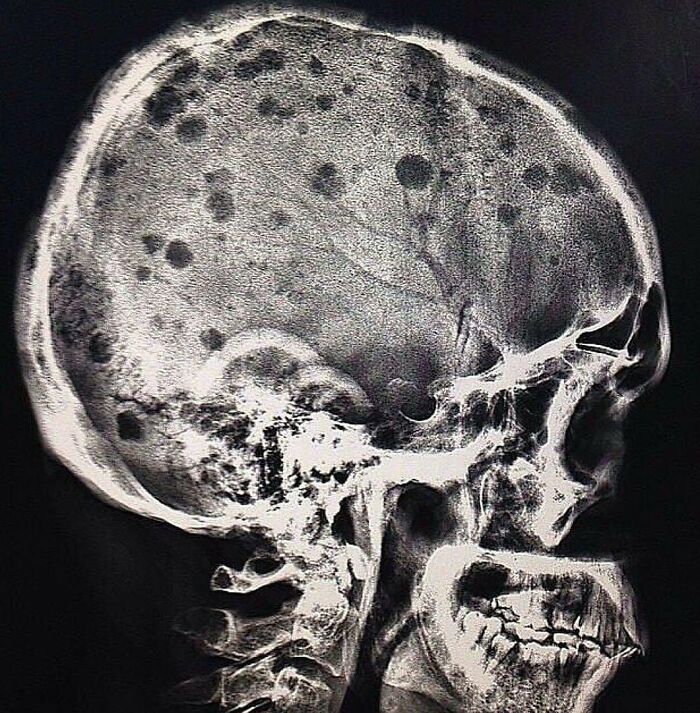

Lateral view skull radiograph of a patient with multiple myeloma

The classic radiographic appearance of multiple myeloma is that of multiple, small, well-circumscribed, lytic, punched-out, round lesions within the skull, spine, and pelvis. The pattern of lytic or punched-out radiolucent lesions on the skull have been described as resembling raindrops hitting a surface and splashing. How would you manage a patient with multiple myeloma?